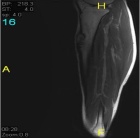

17 year old male c/o left shin pain. He is active in sports. First noted pain while running and with activities. Pain has been intermittent over 9 month period but more constant recently. A palpable lump is present on the left tibia which has not changed in size.